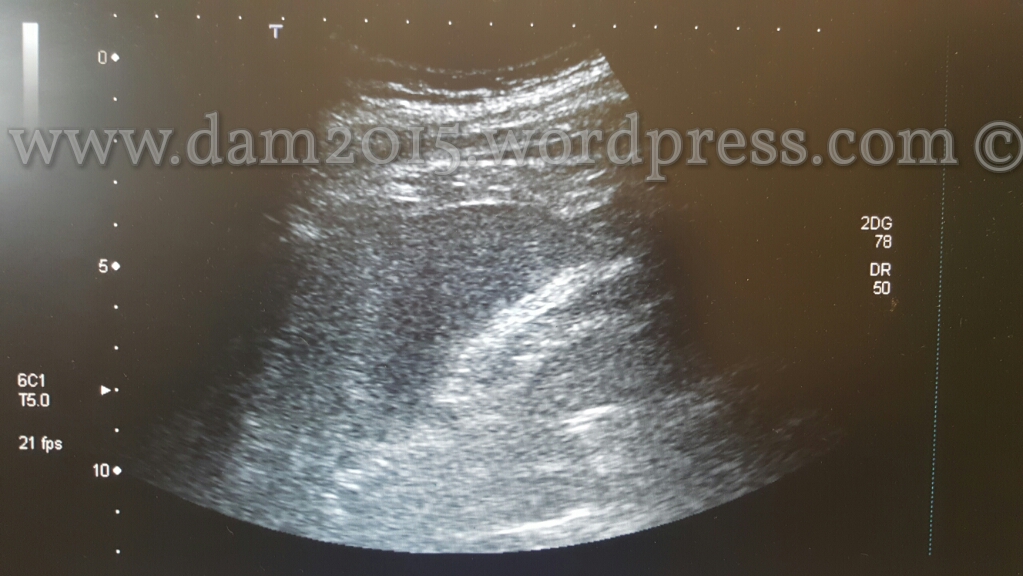

Pz uomo, 56anni.

Incidente stradale moto-auto.

Rottura di milza in due tempi. Emoperitoneo.

Splenectomia.